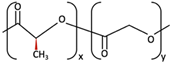

| 1 | PGA |  [39] [39] | High [29] | High [59] | − [59] | 4–12 months [60] | Tissue engineering. Drug-delivery systems [61] | |

| PLA | PLLA |  [62] [62] | High [63] | High [64] | − [51] | > 3.5 years [65] | Tissue engineering. Drug-delivery systems. Fixation devices [66] | |

| PDLA |  [62] [62] | High [63] | High [64] | − [64] | Longer than PLLA [34] | Tissue engineering. Drug-delivery systems, [66] | ||

| PDLLA |  [62] [62] | Lower than PLLA [37] | High [64] | − [64] | 12–30 months [37] | Tissue engineering. Drug-delivery systems [66] | ||

| 2 | PLLA/PGA |  [67] [67] | High [37] | High [68] | − [50] | 12–18 months [44] | Tissue engineering. Drug-delivery systems. Fixation devices [66] | |

| 3 | u-HA/PDLLA | Ca10(PO4)6(OH)2 +  | Low [54] | High [55] | + [56] | 12–18 months [69] | Tissue engineering. Fixation devices [70] | |

| u-HA/PLLA | Ca10(PO4)6(OH)2 +  | Higher than PLLA [19] | High [19] | + [19] | > 5 years [49] | Tissue engineering. Fixation devices [70] | ||

| 4 | u-HA/PLLA/PGA | Ca10(PO4)6(OH)2 +  | Similar to u-HA/PLLA [71] | High [72] | + [71] | 2–3 years [73] | Tissue engineering. Fixation devices [73] | |